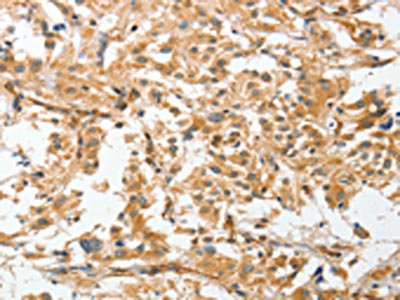

The image on the left is immunohistochemistry of paraffin-embedded Human thyroid cancer tissue using CSB-PA580017(ANGPTL7 Antibody) at dilution 1/30, on the right is treated with fusion protein. (Original magnification: ×200)

The image on the left is immunohistochemistry of paraffin-embedded Human liver cancer tissue using CSB-PA580017(ANGPTL7 Antibody) at dilution 1/30, on the right is treated with fusion protein. (Original magnification: ×200)